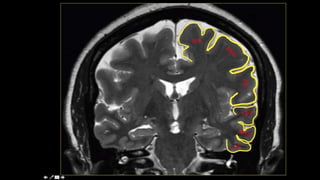

SULCI & GYRI

SULCUS IS THE DEPRESSION [VALLEYS]

AND

GYRUS IS THE RIDGE [HILLS]

Fissure/sulcus Importance

• Interhemispheric fissure • Separates two lobes

 Sylvian fissure/ Lateral

Sulcus

 Frontal to temporal

 Central sulcus  Frontal to parietal

 Callosal sulcus

 Cingulate sulcus

 Interparietal sulcus

 Parieto occipital sulcus

 Calcarine sulcus

12

6

Interhemispheric

fissure

1

3

2

4

5

Superior frontal

Pre central sulcus

Central sulcus

Post central

IPIO

Interhemispheric fissure

The central sulcus-The sigmoid hook

The pars bracket sign- Parieto occipital sulcus

Fish tail- parieto occipital sulcus

Pars marginalis

The bifid sulcus

The intraparietal sulcus